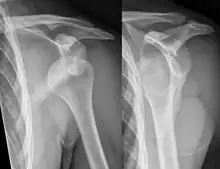

A shoulder dislocation often occurs as a result of a fall onto an outstretched arm or onto the shoulder.[3] Diagnosis is typically based on symptoms and confirmed by X-rays.[2] They are classified as anterior, posterior, inferior, and superior with most being anterior.[2][1]

A diagnosis of shoulder dislocation is often suspected based on the person's history and physical examination. Radiographs are made to confirm the diagnosis. Most dislocations are apparent on radiographs showing incongruence of the glenohumeral joint. Posterior dislocations may be hard to detect on standard AP radiographs, but are more readily detected on other views. After reduction, radiographs are usually repeated to confirm successful reduction and to detect bone damage. After repeated shoulder dislocations, an MRI scan may be used to assess soft tissue damage. In regards to recurrent dislocations, the apprehension test (anterior instability) and sulcus sign (inferior instability) are useful methods for determining predisposition to future dislocation.

In over 95% of shoulder dislocations, the humerus is displaced anteriorly.[7] In most of those, the head of the humerus comes to rest under the coracoid process, referred to as sub-coracoid dislocation. Sub-glenoid, subclavicular, and, very rarely, intrathoracic or retroperitoneal dislocations may also occur.[8]

Anterior dislocations are usually caused by a direct blow to, or fall on, an outstretched arm. The person typically holds his/her arm externally rotated and slightly abducted.